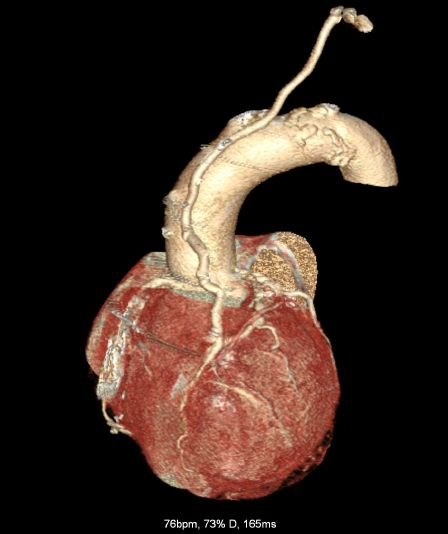

CT Heart